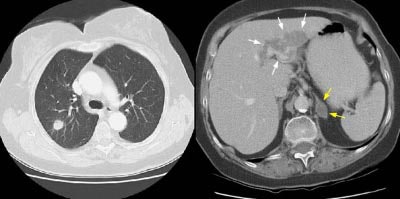

Example 1: False-positive exam -- this patient had a right upper lobe squamous-cell carcinoma. The mass is adjacent to the superior vena cava. Abnormal mediastinal N2 (yellow arrow) nodes were identified by the staging CT exam. Contralateral N3 nodes (white arrows) were borderline abnormal by size criteria. The patient underwent medianstinoscopy and anterior mediastinotomy (Chamberlain procedure) for pre-operative staging -- both of which were negative for malignant cells. The patient had underlying interstitial lung disease which has been associated with the presence of reactive mediastinal adenopathy. At surgery the patient was found to have ipsilateral hilar adenopathy (N1) and parietal pleural invasion (T3 tumor) or a stage IIIA.

Example 2: False-negative CT exam -- this patient had an adenocarcinoma in the right upper lobe that measured less than 3 cm in size (T1 lesion). The ipsilateral mediastinal nodes identified by staging CT were not pathologic by size criteria. The surgical team elected to proceed to thoracotomy without mediastinoscopy. At surgery, the small right paratracheal nodes which measured less than 1 cm where found to contain microscopic foci of tumor (N2 nodes). The patient was staged histopathologically as T1N2M0 (Stage IIIA).